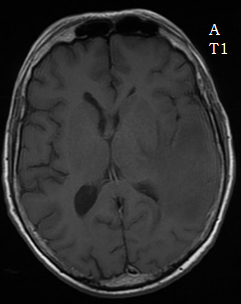

En IRM, comme la nuit, tous les chats sont gris

Dr Arnault Tauziède-Espariat AP-HP Lariboisière - Paris

Données cliniques :

• Patient âgé de 59 ans adressé en urgence pour des céphalées évoluant depuis une semaine accompagnées de troubles du langage à type de manque du mot.

• Principaux antécédents : syndrome d’Alport compliqué d’insuffisance rénale chronique ayant nécessité une greffe rénale en 1983.

• Scanner cérébral : lésion cérébrale temporale gauche gauche, avec un effet de masse et un œdème périlésionnel.

• Hospitalisation en service de neurochirurgie et bilan.